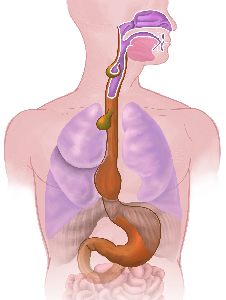

Detailreiche Fotografien aus der medizinischen Praxis ergänzen die Texte; moderne, genaue,

wissenschaftliche Zeichnungen geben Einblick in die Anatomie und die Funktion der Lunge und

anderer Organe.